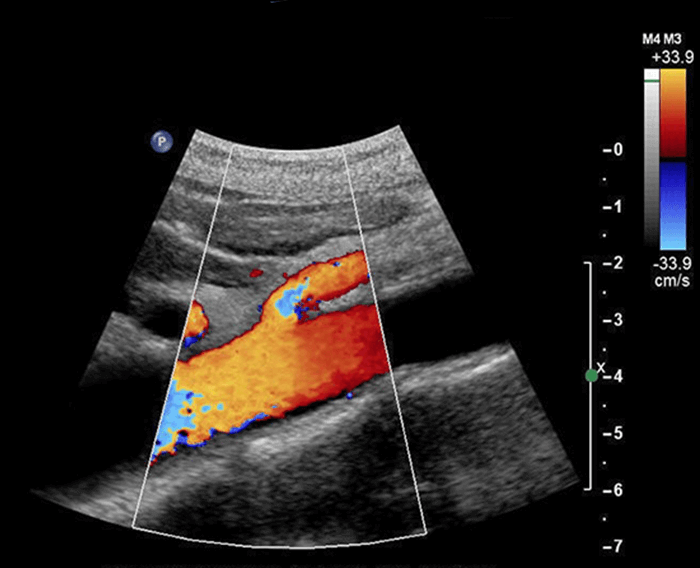

Ct Angiography is a non-invasive method that employs X-rays to implement detailed images of hemoglobin vessels progressing to the heart and lungs, kidneys, and other organs. Doctors suggest that it should not be used in cases where preliminary tests such blood parameters or exercise stress tests indicate cardiovascular risk.

Our 3 imaging units provide service in Ahmedabad , Gandhinagar and the surrounding areas with a full range of imaging that includes 1.5 Tesla MRI, CT, digital X Ray, ultrasound, colour Doppler, echocardiography & radiological (conventional & interventional) procedures.